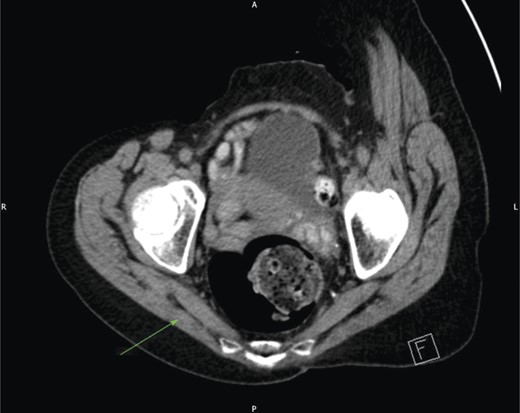

CT scan of the pelvis did not identify a cause for the swelling (Fig. 1). Due to the positional nature of the swelling, a gluteal ultrasound was organized, which revealed a large colonic sciatic hernia (Fig. 2). As the patient had minimal symptoms and was not keen for surgical intervention, a plan for conservative management was agreed and the patient was discharged from clinic.

CT of the patient's pelvis demonstrating a normal right sciatic foramen (arrowed).